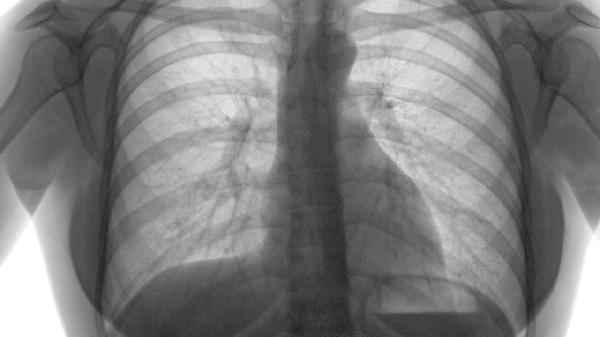

第一秒用力呼气容积占预计值百分比是评估预后的核心指标。当数值低于35%时,机体氧合能力显著下降,右心负荷持续加重,可加速多器官功能衰竭进程。规范使用支气管扩张剂联合长期氧疗能延缓肺功能恶化。

慢性呼吸衰竭与肺源性心脏病是常见致死原因。夜间血氧饱和度持续低于85%会诱发心律失常,需无创通气支持。合并冠状动脉疾病者需严格控制血压和血脂水平。